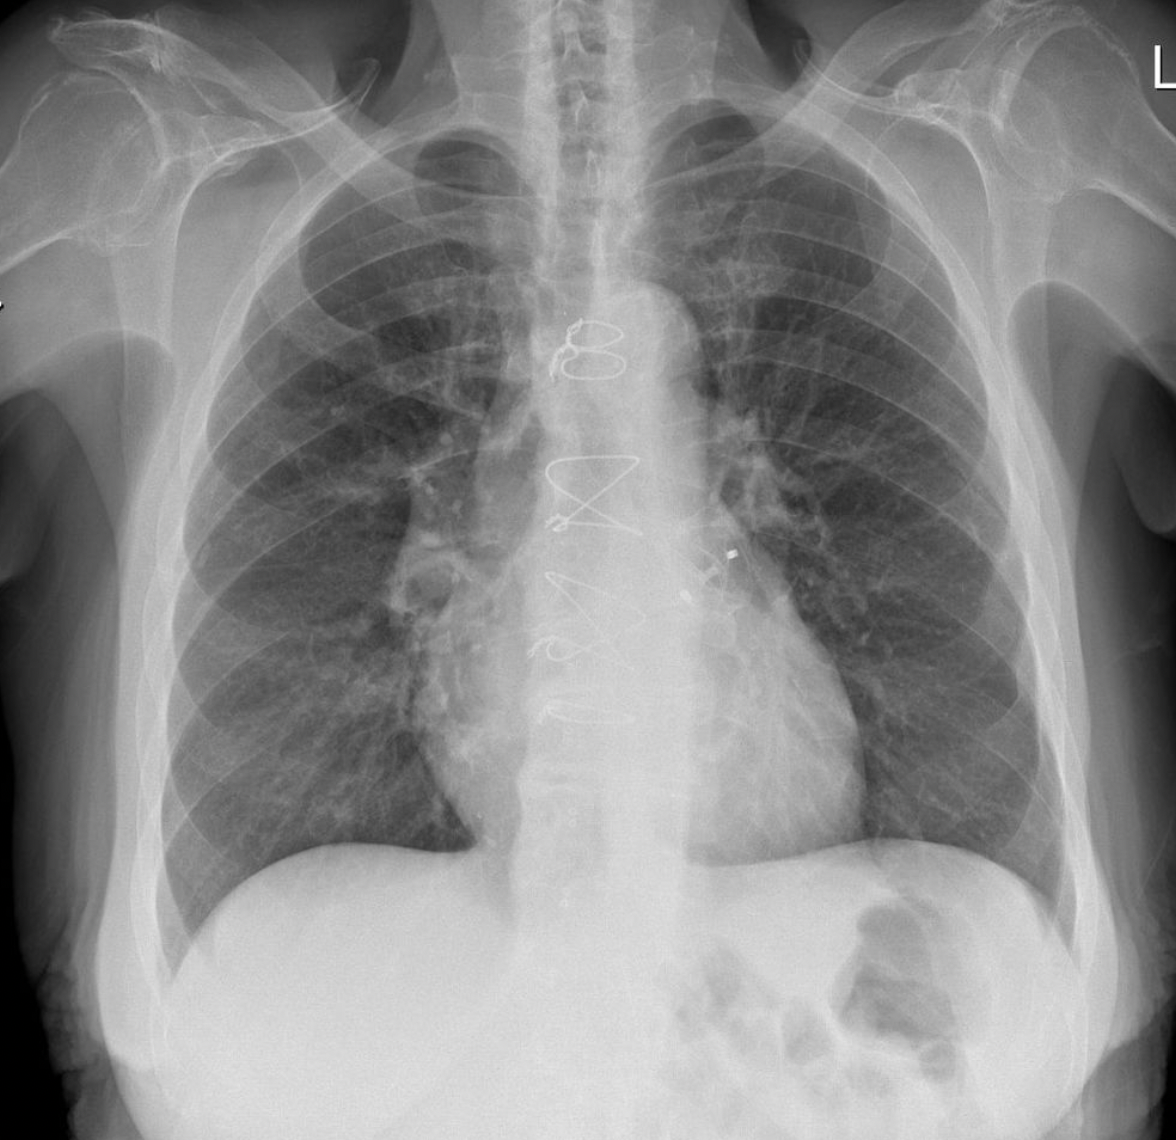

4

Pericardial effusion